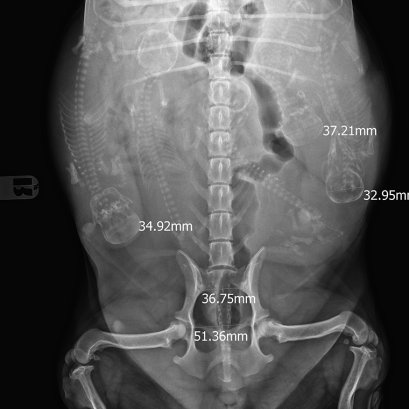

ภาวะคลอดยากในสุนัข (dystocia) เกิดจากการที่แม่สุนัขไม่สามารถคลอดลูกสุนัขออกมาจากช่องเชิงกรานได้ตามธรรมชาติ ซึ่งเป็นภาวะฉุกเฉินที่เป็นสาเหตุการเสียชีวิตได้ทั้งแม่และลูกสุนัข เจ้าของอาจสังเกตอาการที่อาจเข้าข่ายภาวะคลอดยากในเบื้องต้น และให้รีบติดต่อสัตวแพทย์ทันที เพื่อทำการแก้ไขอย่างเร่งด่วน เช่น การผ่าคลอด เป็นต้น